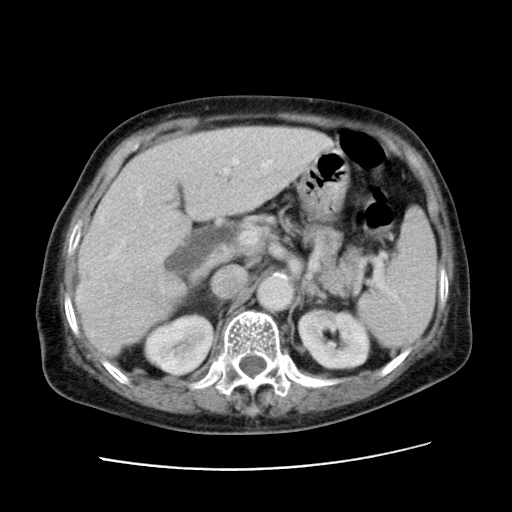

女,77.无不适

肝脏变异、异位胆囊,肝右叶肝内胆管结石并肝内胆管扩张。

肝右叶肝内胆管结石并肝内胆管扩张。

肝右叶肝内胆管结石并肝内胆管扩张

胆总管扩张

肝右叶肝内胆管结石并肝内胆管扩张。胆总管下段梗阻,考虑壶腹部占位。

右侧肝内胆管局限性扩张,其内密度不均匀,扩张的胆管壁增厚,考虑肝内胆管炎合并结石可能性大